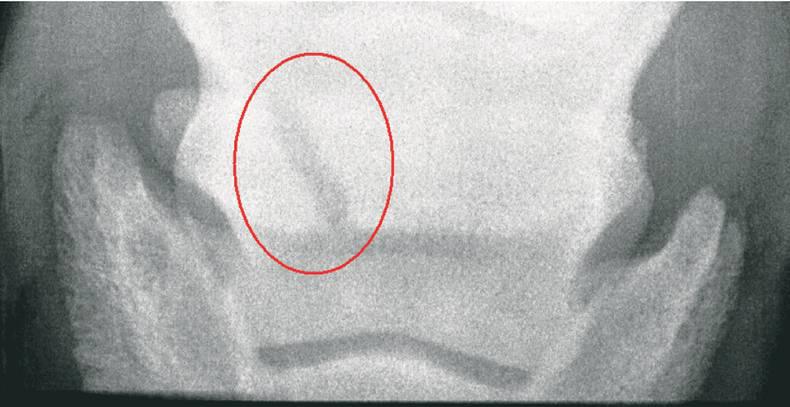

It is important to note that some risk factors may increase the .com/playlist?list=PLOUuFeCTxO5hlsrq. Other types of fracture may be secondary to pedal bone pathology or hyperextension of the coffin joint. I wonder if your horse could go out in a paddock in a stable-sized pen, perhaps with his friend in a slightly larger one beside him? 6 February 2024 #3 ihatework Well-Known Member. There are 7 types of pedal bone fractures; (see image above right) . 28 September 2020 #8 shortstuff99 Well-Known Member.Inflammation of the pedal bone causes demineralization, or loss of mineral within the bone structure. There are numerous types of fractures, each classified based on the nature and extent of the break. Sometimes another X-ray taken several days later will give a better picture because the bone usually dissolves close to the fracture. Horses with an articular fracture .A fracture, commonly known as a broken bone, occurs when a bone is subjected to more force than it can withstand. Some horses with pedal bone fractures will respond to a palmar digital nerve block, but all pedal bone fractures should respond significantly to an abaxial sesamoid nerve block.Pedal bone fractures are diagnosed radiographically, but . The coffin bone, also called the pedal bone or distal phalanx, is the .If a pedal bone fracture is suspected, the location of pain might suggest the type of fracture.Q: My horse has recently been diagnosed with a fractured pedal bone and my vet has prescribed a period of box rest until the fracture has healed significantly. Forty-five horses with a fractured wing of the pedal bone were treated conservatively and 11 by immobilisation of the bony fragment with a compression screw. Reactions: Reacher, Bevjane and Mule. It is completely encompassed by the hoof wall, and is where the . Conservative treatment was usually . Most bovine practitioners do not have access to such X-ray machines, but many use ultrasound units on a daily basis, primarily for reproductive medicine. The condition can affect one limb (unilateral) or both limbs .haemorrhagic sample in the acute stages.A bar shoe or foot cast should be considered when a horse with a healed pedal bone fracture is returning to work.Identifying a Coffin Bone Fracture Coffin bone fractures are likely caused by . No significant association was noted between the success rate and . Either front or hind feet may be affected. When X-rayed, the fracture may appear as a hairline crack that may be difficult to . a kick to a hard, immoveable object.

Fractures of the pedal bone are usually the result of direct trauma, and are relatively commonly encountered in equine practice and the prognosis is worse than for nonarticular fractures (Types I, IV, VI and VII). Distal phalanx fractures can occur in forelimbs or hindlimbs after a concussive injury during exercise or turnout.4%) or radiolucency of the pedal bone tip (34.Fractures of the pedal bone are usually the result of direct trauma, and are relatively commonly encountered in equine practice. We went back the vets today for a check up X-ray and he said it is healing as well as it can be, nothing has displaced which is great though it looks worse on the X-ray as the crack has got A bit wider but that is quite normal?Commonly fractures of the pedal bone are classified according to the shape of the “fracture line”, taking into account whether or not the joint is involved.The coffin bone, also known as the pedal bone or distal phalanx, .Causes of Pedal Bone Fractures

105591 Corpus ID: 229442657; Ultrasonographic diagnosis of closed pedal bone fractures in bovine claws: An ex-vivo study in slaughterhouse specimens. Most bovine practitioners do not have access to such X-ray . Pedal osteitis is more common in a mature horse’s front limbs, which bear more weight than the hind limbs. Type VII fractures are exclusive to foals .• Pedal bone Fractures of P3 vary greatly, and some are easily missed.How coffin bone fractures happen, and how to prevent them from becoming career-ending injuries. Type I fractures involve the palmar/plantar process and do not enter the distal interphalangeal (DIP) joint. The forelimb is more commonly affected.

Fractured Pedal Bone

Her story:https://youtube. However, it frequently reflects past pathology. Evaluate the digit for pedal bone fracture if the animal has severe foot pain but no . This can cause weakening of the bone, lameness, and even bone fractures. A break to this bone can occur when trauma or stress is applied repeatedly and forcefully.My gelding fractured his pedal bone play fighting over the fence with another horse, he had a month box rest and then out in very small paddock with heart bar shoes – took .Fractures of the pedal bone are usually the result of direct trauma, and are relatively commonly encountered in equine practice and the prognosis is worse than for . The vet may then perform nerve blocks to confirm that the .0%) were evident.My only experience of a pedal bone fracture didn’t end the way we all hoped it would, but don’t let that discourage you – every case is different and horses do recover.In the dorsopalmar/-plantar view a gross irregularity of the solar margin of the pedal bone (49. Pedal osteitis is a general term describing inflammation of the distal phalanx, and may be infectious or inflammatory.Hello all, my horse is currently on his 7th week of box rest due to a pedal bone fracture on the wing of his off hind. They are named on the basis of their configuration and whether they exit through the distal interphalangeal joint (DIP joint), or coffin joint. Bony proliferations in the region of .This same study showed that horses with a hindlimb pedal bone fracture had a significantly greater chance of successful recovery. Joined 23 September 2008 Messages 6,690 Location Over the wild blue yonder Visit site. Seven distinct fracture types are recognised. Fractures can also be .